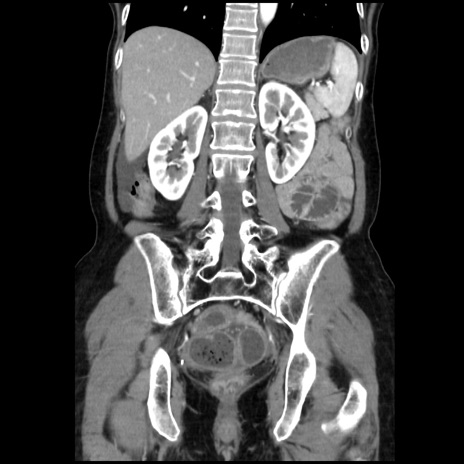

症例32(冠状断像)

【症例】40歳代 女性

【主訴】上腹部痛、嘔気・嘔吐

【現病歴】約9時間前頃から急に上腹部痛、嘔気、嘔吐が出現。改善しないため救急要請。

【既往歴】子宮頚癌(広汎子宮全摘術、放射線療法)、腸閉塞

【身体所見】腹部:平坦、軟、腸雑音亢進、上腹部を中心に腹部全体に圧痛あり。

【データ】WBC 8400、CRP 0.03